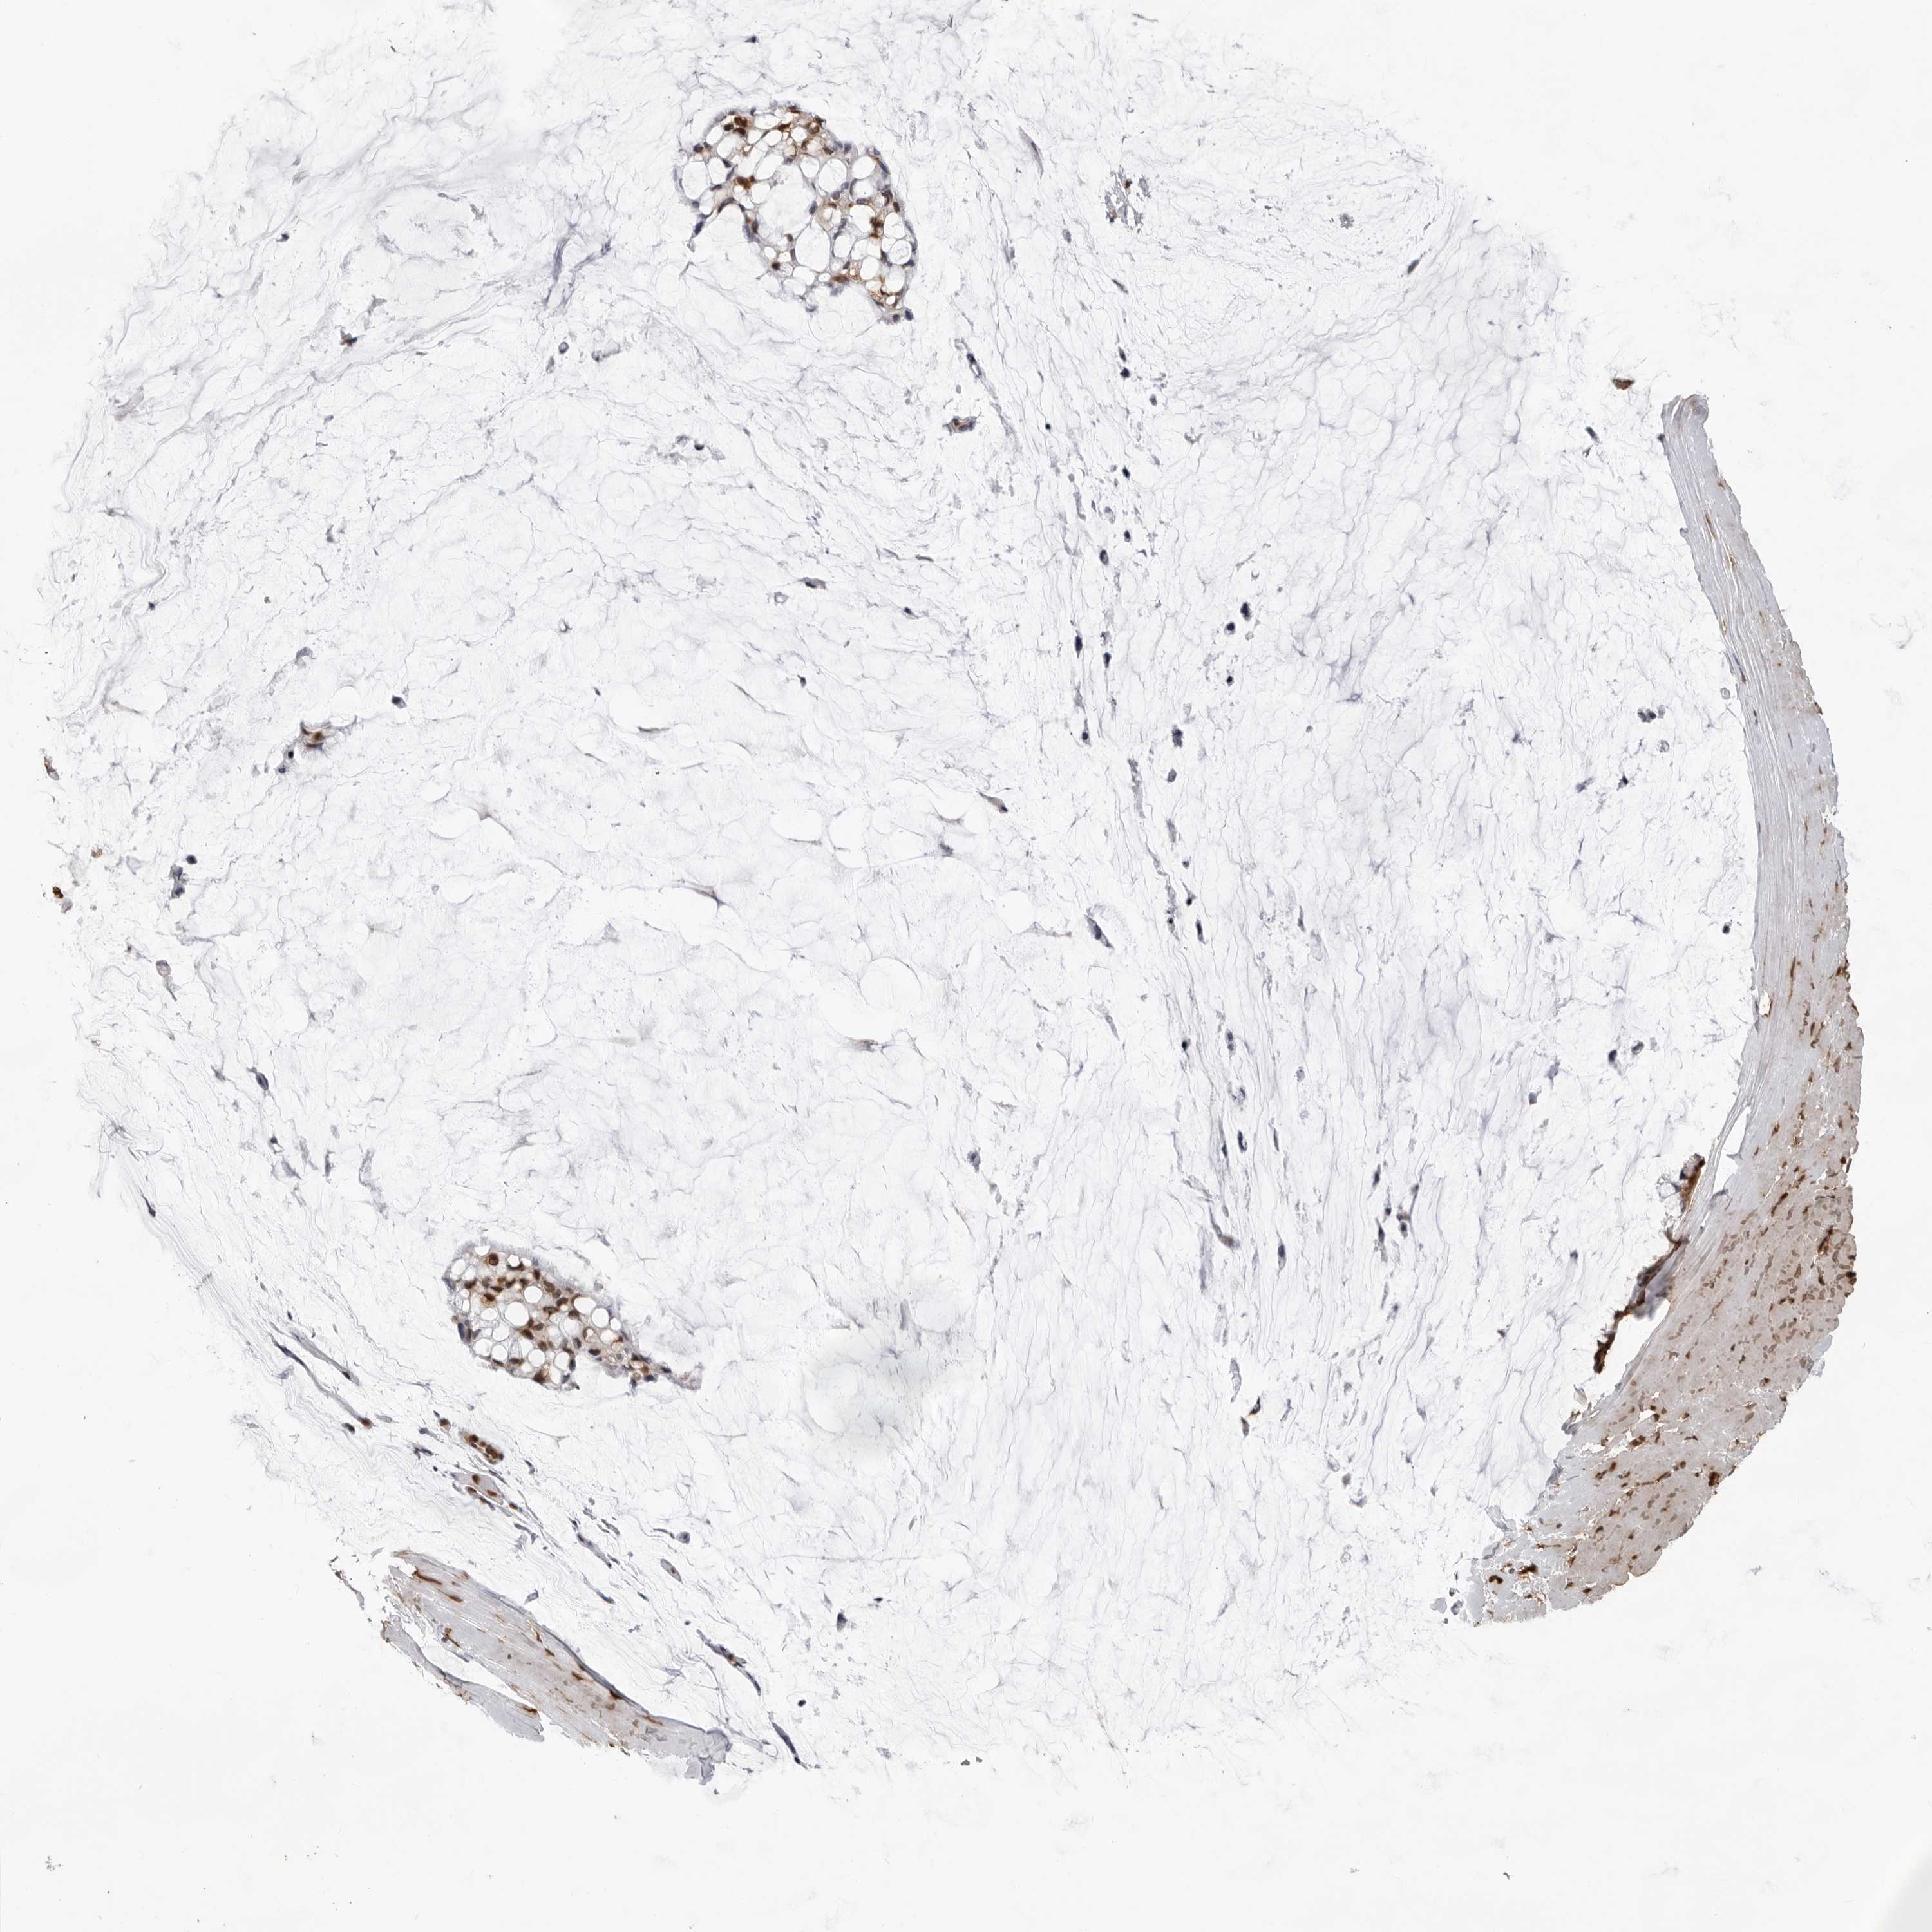

OVARIAN CANCER - Protein expressioni

A mouse-over function shows sample information and annotation data. Click on an image to view it in a full screen mode. Samples can be filtered based on level of antibody staining by selecting one or several of the following categories: high, medium, low and not detected. The assay and annotation is described here.

Note that samples used for immunohistochemistry by the Human Protein Atlas do not correspond to samples in the TCGA dataset.

Antibody stainingi

Antibody staining in the annotated cell types in the current human tissue is reported as not detected, low, medium, or high, based on conventional immunohistochemistry profiling in selected tissues. This score is based on the combination of the staining intensity and fraction of stained cells.

Each image is clickable and will lead to virtual microscopy that enables deeper exploration of all samples and also displays staining intensity scores, fraction scores and subcellular localization as well as patient and tissue information for each sample.

Antibody HPA024037

Antibody HPA065325

Antibody HPA074591

Antibody CAB025417

Staining

High

Medium

Low

Not detected

Intensity

Strong

Moderate

Weak

Negative

Quantity

>75%

75%-25%

<25%

None

Location

Nuclear

Cytoplasmic/membranous

Cytoplasmic/membranous,nuclear

Cystadenocarcinoma, serous, NOS

Carcinoma, endometroid

Cystadenocarcinoma, mucinous, NOS

Carcinoma, NOS